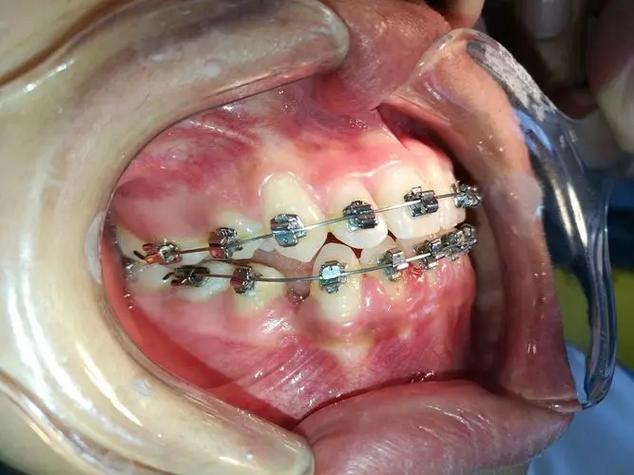

- 托槽粘接:演示托槽定位的关键标志点(如上颌中切牙切缘中点、下颌第一磨牙颊面管中心),结合口内视频展示酸蚀、涂粘接剂、放置托槽的细节,强调定位精度对矫治效果的影响。